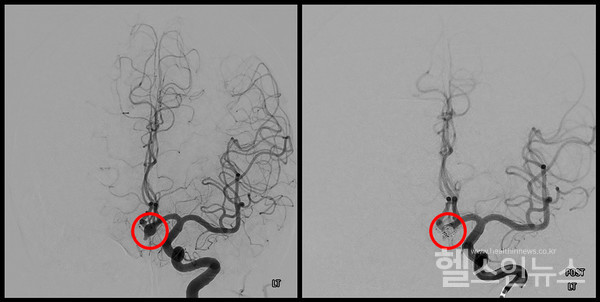

치료방법은 뇌동맥류의 크기, 모양, 위치 및 환자의 상태를 고려하여 선택하게 된다. 머리를 열고 수술하는 개두술, 클립 결찰술, 뇌혈관 내부로 접근하는 코일 색전술이 있다. 각 방법에 장단점은 있지만, 치료의 수준이 계속 발전하고 있어 높은 완치율을 보이고 있다. 최근엔 미용까지 고려해서 수술할 정도로 안전하게 치료를 하고 있다. 따라서 전문가의 의견에 따라 환자별 맞는 치료법으로 신속하게 치료하는 것이 중요하다.